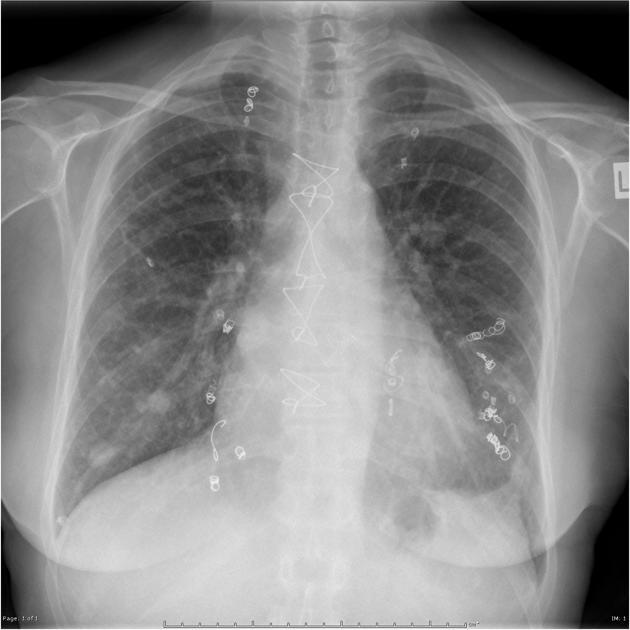

Patient with recurrent epistaxis. Diagnosis?

Multiple (coiled) AVMs in hereditary hemorrhagic telangiectasia (Osler-Weber-Rendu). Telangiectasia, recurrent epistaxis, and multiple-organ AV malformations.

Autosomal-dominant disorder of variable penetrance, chromosomes 9 and 12.